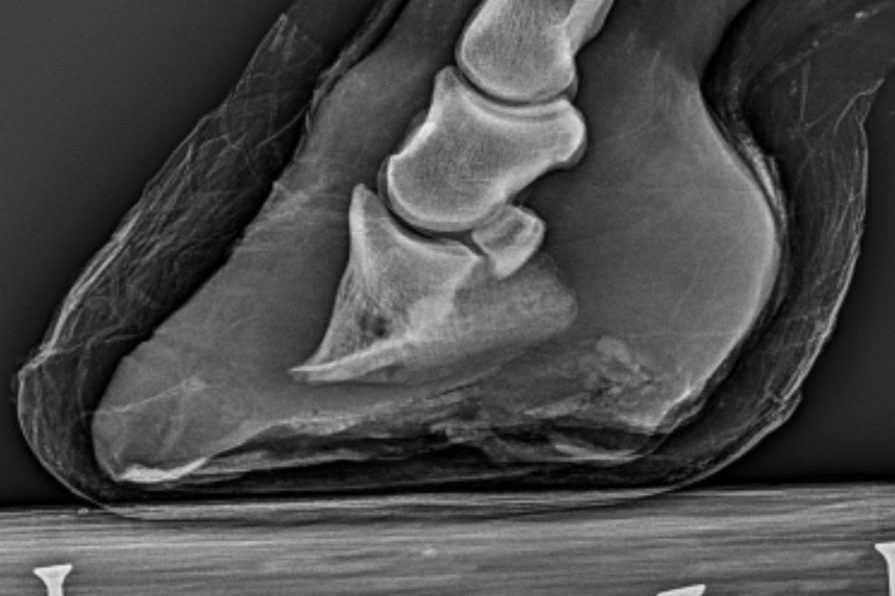

- Digitales Röntgen: Für schnelle und hochauflösende Bildgebungen zur präzisen Diagnose von orthopädischen Problemen.